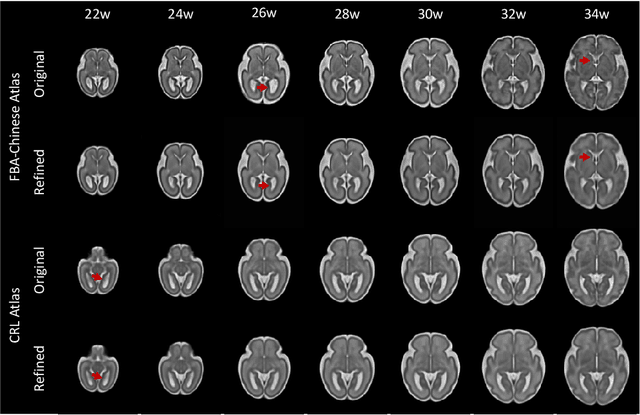

Abstract:Longitudinal fetal brain atlas is a powerful tool for understanding and characterizing the complex process of fetus brain development. Existing fetus brain atlases are typically constructed by averaged brain images on discrete time points independently over time. Due to the differences in onto-genetic trends among samples at different time points, the resulting atlases suffer from temporal inconsistency, which may lead to estimating error of the brain developmental characteristic parameters along the timeline. To this end, we proposed a multi-stage deep-learning framework to tackle the time inconsistency issue as a 4D (3D brain volume + 1D age) image data denoising task. Using implicit neural representation, we construct a continuous and noise-free longitudinal fetus brain atlas as a function of the 4D spatial-temporal coordinate. Experimental results on two public fetal brain atlases (CRL and FBA-Chinese atlases) show that the proposed method can significantly improve the atlas temporal consistency while maintaining good fetus brain structure representation. In addition, the continuous longitudinal fetus brain atlases can also be extensively applied to generate finer 4D atlases in both spatial and temporal resolution.